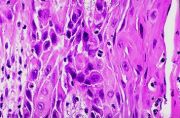

| 2021年12月10日 (五) 13:17 | 16号切片-鳞癌-镜下观2.jpg (文件) |  |

50 KB | Cirno.9 | 基于MsUpload的文件上传 | 1 |

| 2021年12月10日 (五) 13:17 | 16号切片-鳞癌-镜下观1 .jpg (文件) |  |

50 KB | Cirno.9 | 基于MsUpload的文件上传 | 1 |

| 2021年12月10日 (五) 13:17 | 16号切片-鳞癌(角化珠)-镜下观2.jpg (文件) |  |

66 KB | Cirno.9 | 基于MsUpload的文件上传 | 1 |

| 2021年12月10日 (五) 13:17 | 16号切片-鳞癌(角化珠)-镜下观1.jpg (文件) |  |

80 KB | Cirno.9 | 基于MsUpload的文件上传 | 1 |

| 2021年12月10日 (五) 13:16 | 16号切片-鳞癌(癌巢)-镜下观2.jpg (文件) |  |

62 KB | Cirno.9 | 基于MsUpload的文件上传 | 1 |

| 2021年12月10日 (五) 13:16 | 16号切片-鳞癌(癌巢)-镜下观1.jpg (文件) |  |

180 KB | Cirno.9 | 基于MsUpload的文件上传 | 1 |